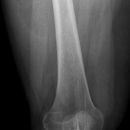

Femurschaftfraktur